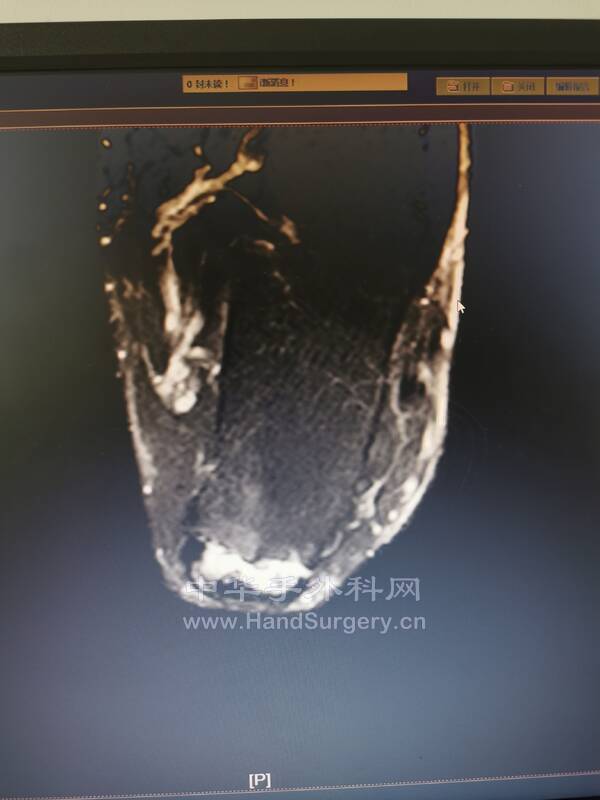

比如这个患者

跟腱止点断裂

再看核磁影像,手术所见历历在目